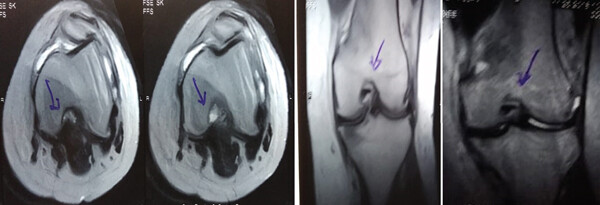

MRI檢查發(fā)現(xiàn)半月板損傷處修復(fù):3D MRI 顯示 2 年時(shí)半月板撕裂難以辨別。

移植滑膜間充質(zhì)干細(xì)胞修復(fù)前后的3D MRI圖像

結(jié)論:滑膜間充質(zhì)干細(xì)胞移植后,2年的隨訪中,患者的關(guān)節(jié)功能改善,MRI檢查發(fā)現(xiàn)半月板損傷處恢復(fù),沒有發(fā)生導(dǎo)致研究終止的重大不良事件。可以達(dá)到干細(xì)胞治療半月板損傷長(zhǎng)期療效的目標(biāo)。